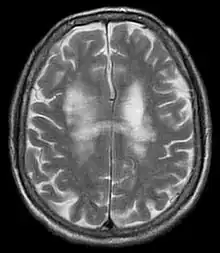

| T2-weighted MRI showing progressive multifocal leukoencephalopathy | |

PML is diagnosed in a patient with a progressive course of the disease, finding JC virus DNA in spinal fluid together with consistent white-matter lesions on brain magnetic resonance imaging (MRI); alternatively, a brain biopsy is diagnostic[1] when the typical histopathology of demyelination, bizarre astrocytes, and enlarged oligodendroglial nuclei are present, coupled with techniques showing the presence of JC virus.[12]

Characteristic evidence of PML on brain CT scan images are multifocal, noncontrast enhancing hypodense lesions without mass effect, but MRI is far more sensitive than CT.[12] The most common area of involvement is the cortical white matter of frontal and parieto occipital lobes, but lesions may occur anywhere in the brain, such as the basal ganglia, external capsule, and posterior cranial fossa structures such as the brain stem and cerebellum.[12] Although typically multifocal, natalizumab-associated PML is often monofocal, predominantly in the frontal lobe.[12]